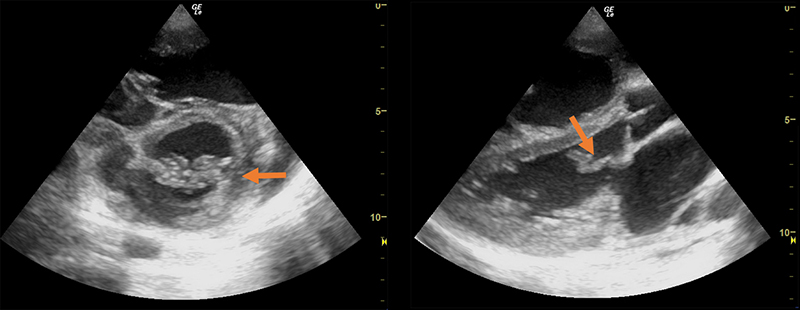

- Liver Lobes - The left and right lobes are divided by the middle hepatic vein, and the caudate lobe lies posterior to the left lobe, between the inferior vena cava (IVC) posteriorly and the ligamentum venosum anteriorly.

Figure 7. Transverse subxiphoid view of the liver. The middle hepatic vein divides the left and right lobes of the liver. The caudate lobe is located posterior to the left lobe. (R,M,L = Right, Middle, Left hepatic veins, respectively. IVC = Inferior Vena Cava)

Figure 8. Transverse subxiphoid view of the liver. Hepatic veins (orange arrows) are straight with thin walls, whereas portal veins (blue arrows) have bright walls and are more tortuous.